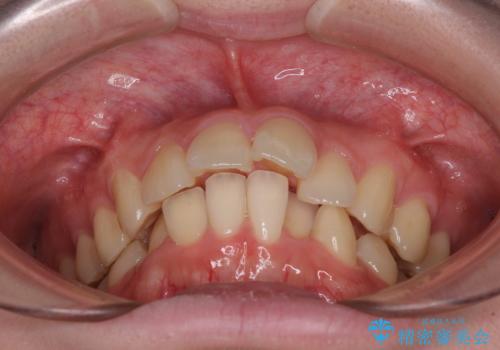

- 下顎の前歯が上顎の歯肉に咬みこむくらいに突出した上顎前歯を気にして来院された患者様です。

口元の突出感はないものの、上顎前歯が前方に傾斜して突出しており、前後に大きなズレがあり非常に深い咬み合わせとなっていました。